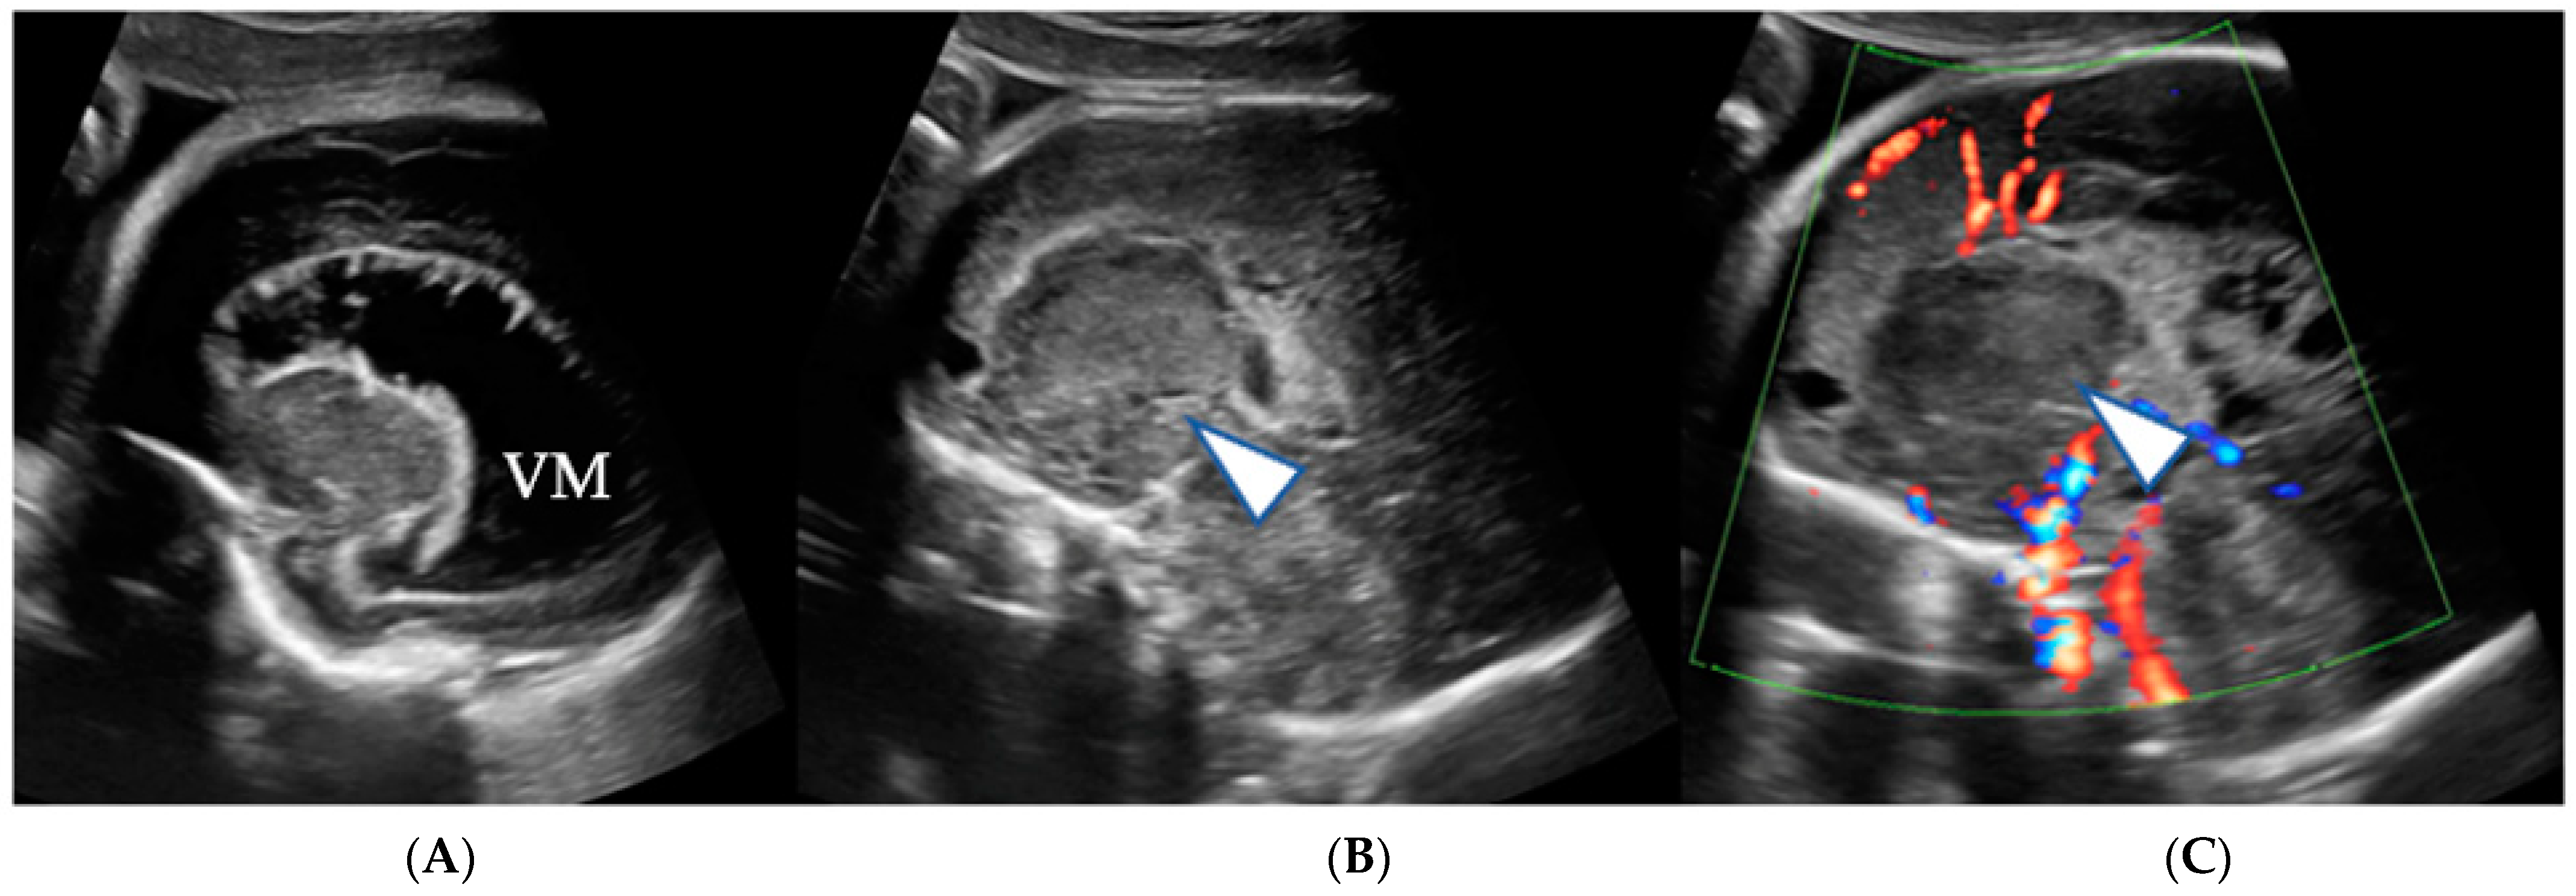

2. Case Series